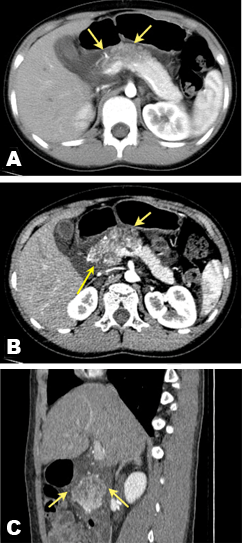

An 11-year-old boy was admitted to our hospital in May 2016 because of the edema of face and extremities, and anorexia in the previous four years. He is 152 cm and 52 kg. He also complained a mild abdominal pain for a day. He had soft stool daily. The abdominal ultrasound showed a multiloculated anechoic cystic mass adjacent to the head and neck of the pancreas. A contrast-enhanced computed tomography (CT) scan revealed a 7.7×4.5 cm cystic lesion involving head and neck of the pancreas (Figure 1), and also showed diffuse thickening of gallbladder wall. No evidence of pancreatic or biliary duct dilation was seen.

Figure 1: Suspected cystic mass in the pancreatic head and neck as seen on computed tomography scans (Yellow arrows, suspected cystic mass). Axial CT with no enhancement (A) or with two-phase contrast, (B) exhibiting an interconnecting cysts separated by septa in the pancreatic head and neck. Reconstruction in sagittal projection, and arterial phase demonstrating poor enhancement of the lesion (C).